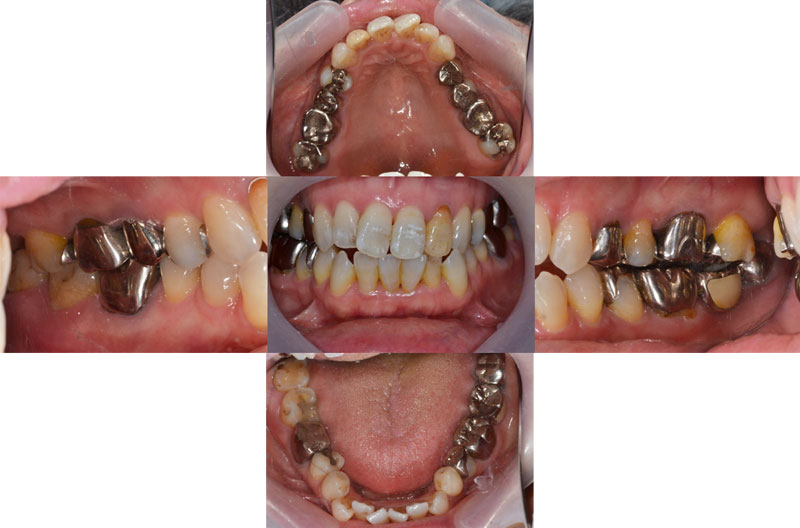

| 術後 |

|---|

![]() |

年齢:36歳

主訴:歯が痛い

初診時の診断と治療方針

初診時の口腔内写真です。主訴の歯の痛みは、斜めに生え噛む面が虫歯になっている右下親知らずであることが分かります。また、その他の部位にも多くの修復物や歯列の乱配を認め、う蝕と歯周病共にリスクが高いことが考えられます。

さらに、歯列の乱配だけでなく傾斜、はまり込みを認めます。 X線写真では全顎的な軽度の歯周病の進行、左下には歯根の著しい吸収を認める乳歯も残っています。引き続き医療面接、う蝕や歯周病の詳しい検査を進め、治療方針についてカウンセリングを行った結果、患者様は顎関節の不調も感じており、インプラントや矯正を含めた全顎的な咬合治療を行っていくことになりました。